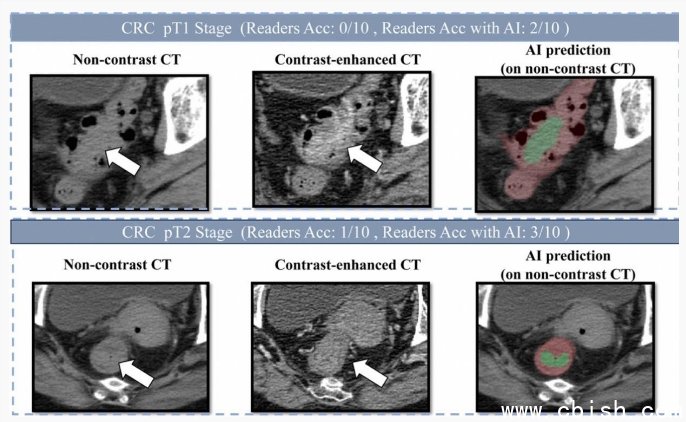

现在不一样了。达摩院的团队用深度学习技术,教会AI在这些“顺手拍”的影像里,精准识别出小于3厘米的早期肿瘤。他们没用花哨的增强扫描,也没要求患者空腹或喝造影剂,而是用“先定位、后诊断”的两步法:先让AI把肠道从一堆器官里“抠”出来,再在每一寸肠壁上仔细“翻找”异常隆起或增厚区域。这套方法专门训练过大量早期小病灶,连医生都容易忽略的微小息肉癌变,也能被它捕捉到。